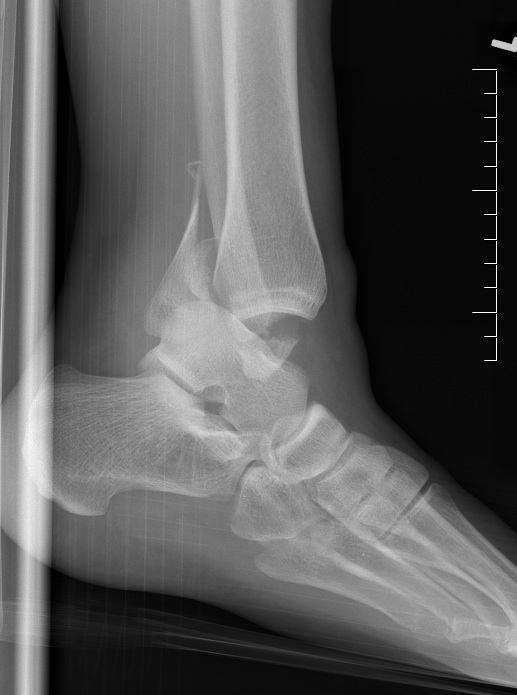

Ankle fractures are one of the more common injuries, and can vary in severity. Most commonly the fracture involves the fibula, although the distal tibia can also be injured. Xray is usually sufficient to diagnose these injuries.